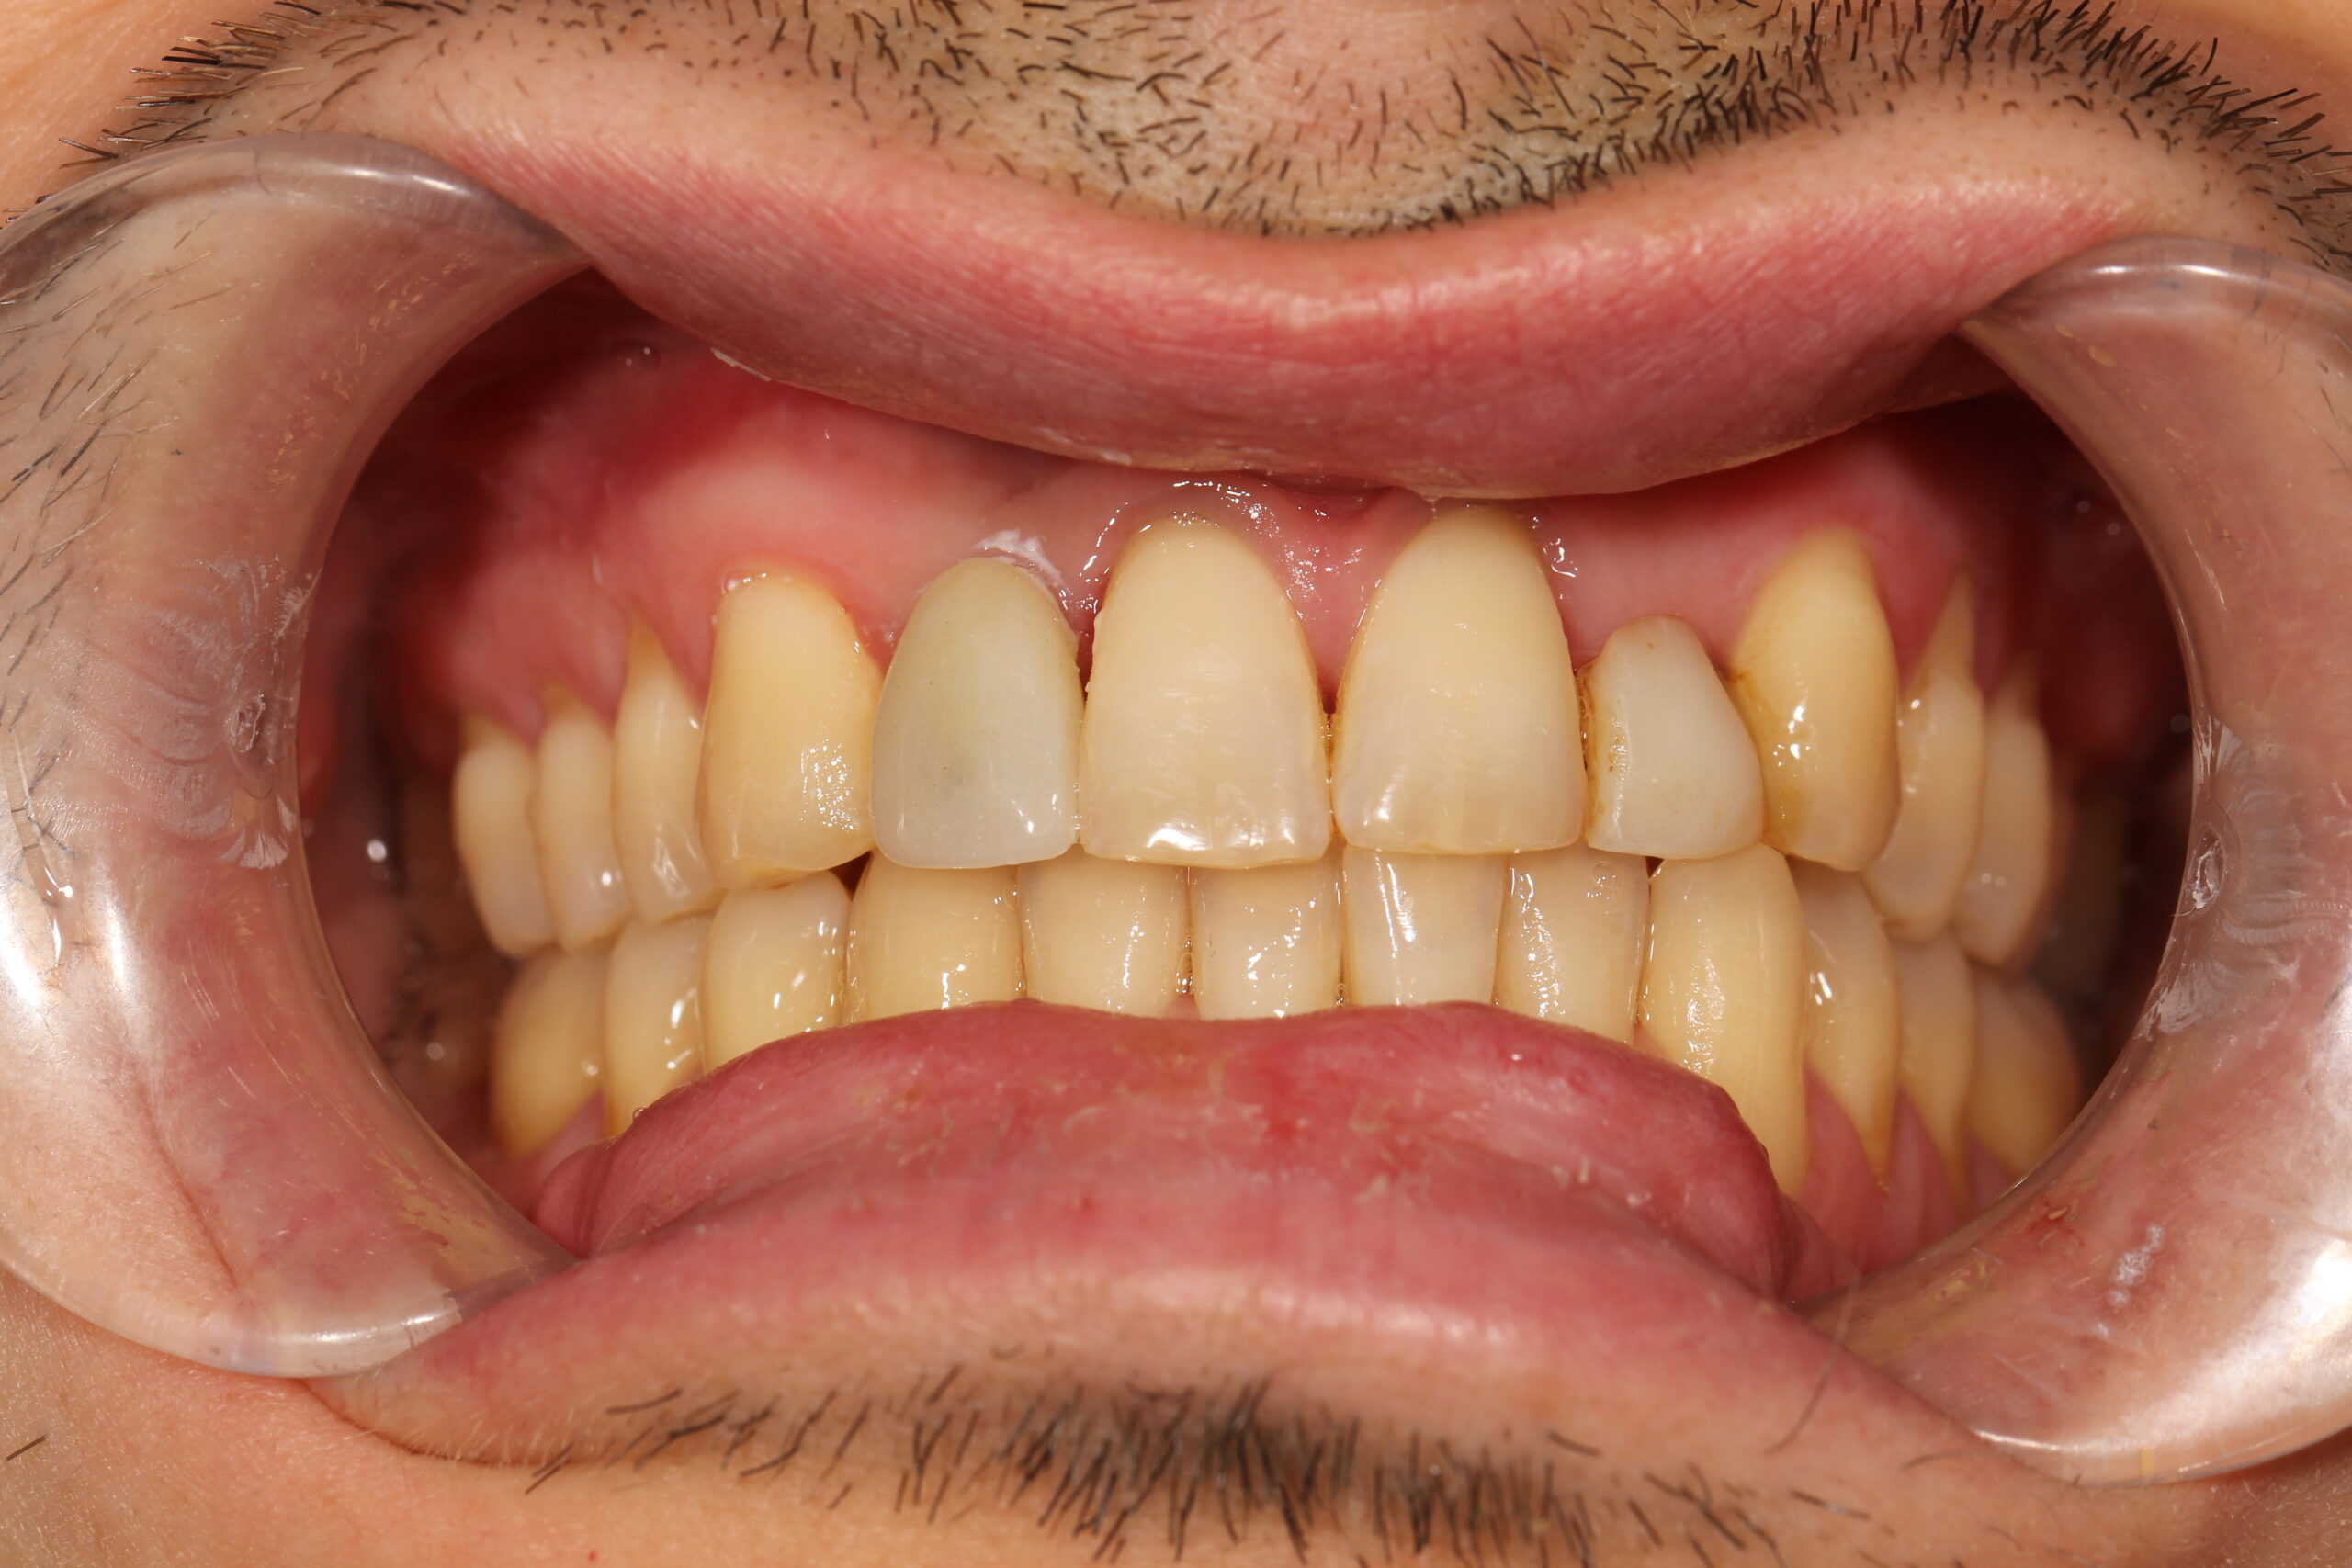

Patient left the office with a temporary crown after his implant placement.

A few weeks later a porcelain crown was cemented to create a beautiful esthetic smile. The outcome in this case was tremendous.